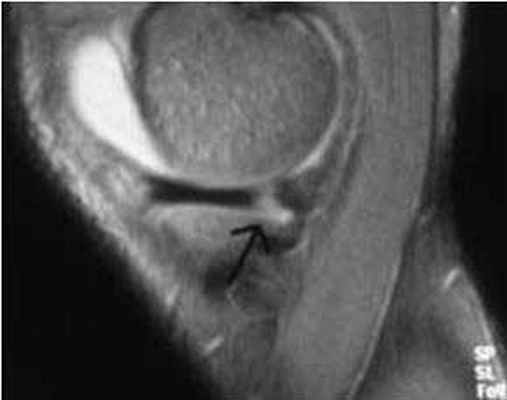

МРТ коленного сустава показывает наличие кисты Бейкера в подколенной ямке (обозначена стрелкой)

Возможно ее обратное развитие вплоть до полного исчезновения, но при условии своевременной диагностики и лечения. При длительном её существовании содержимое кисты затвердевает, формируется спаечный процесс. Возможен ее разрыв, приводящий к появлению острых болей, отеку в подколенной ямке и области голени. В таком случае особое значение приобретает МРТ, которая дает возможность провести дифдиагностику с другими патологиями.

На начальной стадии видна только на МРТ. При прогрессировании может определяться визуально как округлое плотное образование в подколенной области. На этом этапе она уже может вызывать боль при физических нагрузках и дискомфорт при сгибании ноги в колене.